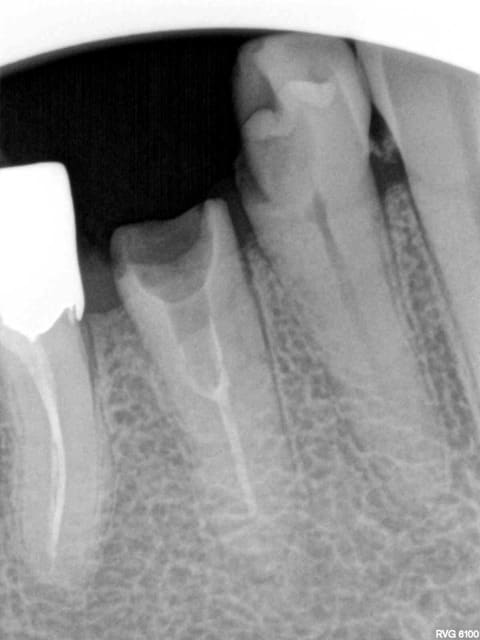

Patiente vue en 2011 et partie dans la nature........

.........Et revenue aujourd'hui en urgence avec un magnifique bridge CCAM-CMU + pulpite sur 26 en option. (bridge 1 mois). Option pèche sur 14 à venir sous l'ic également.

J'y ai collé un amalgame au pouce histoire de faire plus vrai.-)))))

Costaud le full zircone

Tu vois casa je sais faire des cavités d'accès discrètes quand je veux.-))))

Je veux pas être rabat-joie mais tu es sûr que tu n'as pas traité la 6 pour rien, au vu de la lésion en mésial de 4, je pencherais pour une fracture de la racine...

Douleur +++ au froid sur 26 à sauter au plafond + douleurs spontanées, pas de sensibilité percussion sur 14. Mais ca va chauffer un de ces 4 c'est sur.-))))

Pas grave je virerais 14 + taille crayon sur 23 et 26 vu qu'elle n'est plus reconstituable durablement. -))))))

+ Un petit NR sur 25 ou 24. Macho j'ai bon ? -)))))